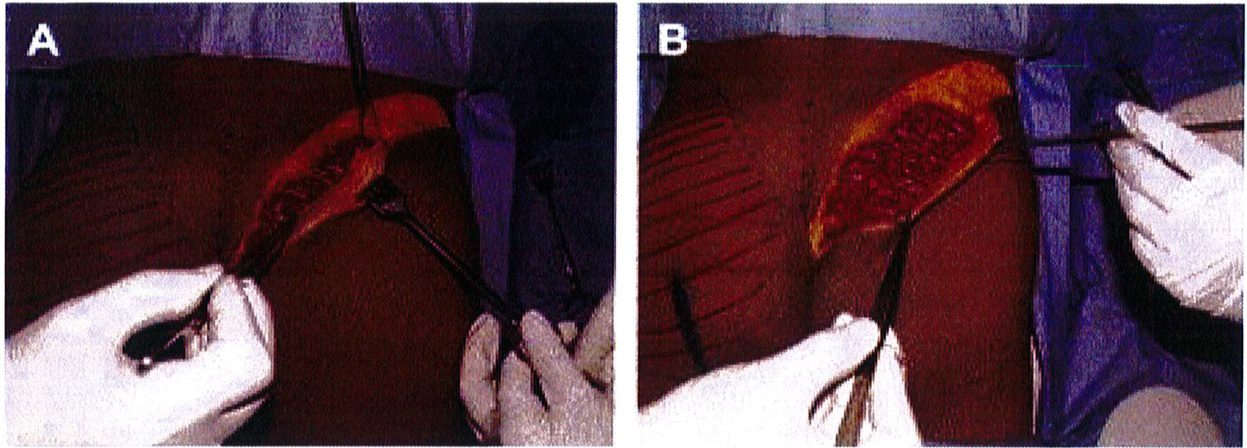

Hình. 8. (A) Phẫu thuật được lên kế hoạch, sử dụng các tiêu bản phù hợp với vùng mông của bệnh nhân với các đường rạch dài 6cm ở hai bên, trên vị trí hậu môn ít nhất 5cm. (B) Đây là hình ảnh bệnh nhân với tiền sử có bệnh lý liên quan vùng mông, đồng thời đã từng thực hiện hút mỡ mông trước đó, nên chúng tôi quyết định đặt đường rạch cao hơn bình thường để tránh các biến chứng.

Hình. 9. Đánh dấu các mốc giải phẫu quan trọng. (A) Đường rạch cân cơ mông lớn bắt đầu từ bờ ngoài xương cùng (B) Bắt đầu bóc tách lớp cân từ đường rạch ban đầu (Trích từ de la Pena JA, Rubio OV, Cano JP, et al. Subfascial Gluteal aug- mentation. Clin Plast Surg 2006;33:411; đã xin phép trước khi đăng tải.)